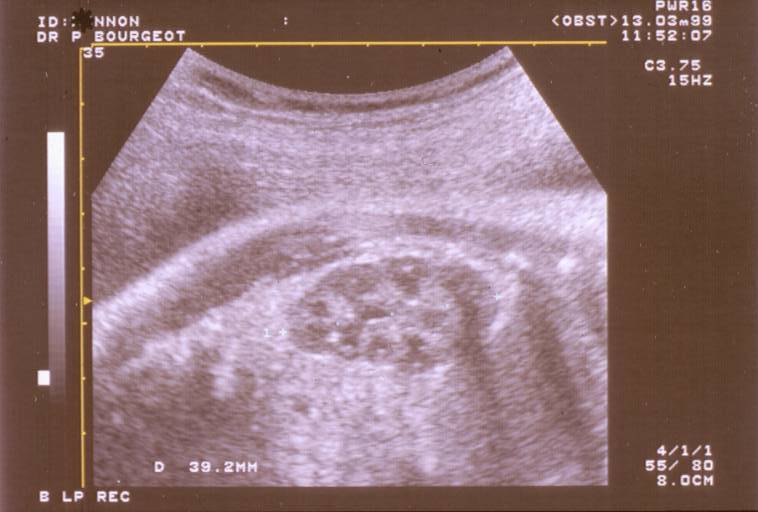

Bilan d’une IRA: voilà l’échographie rénale et des voies urinaires sup; que voit-on?

Dilatation des cavités pyélocalicielles